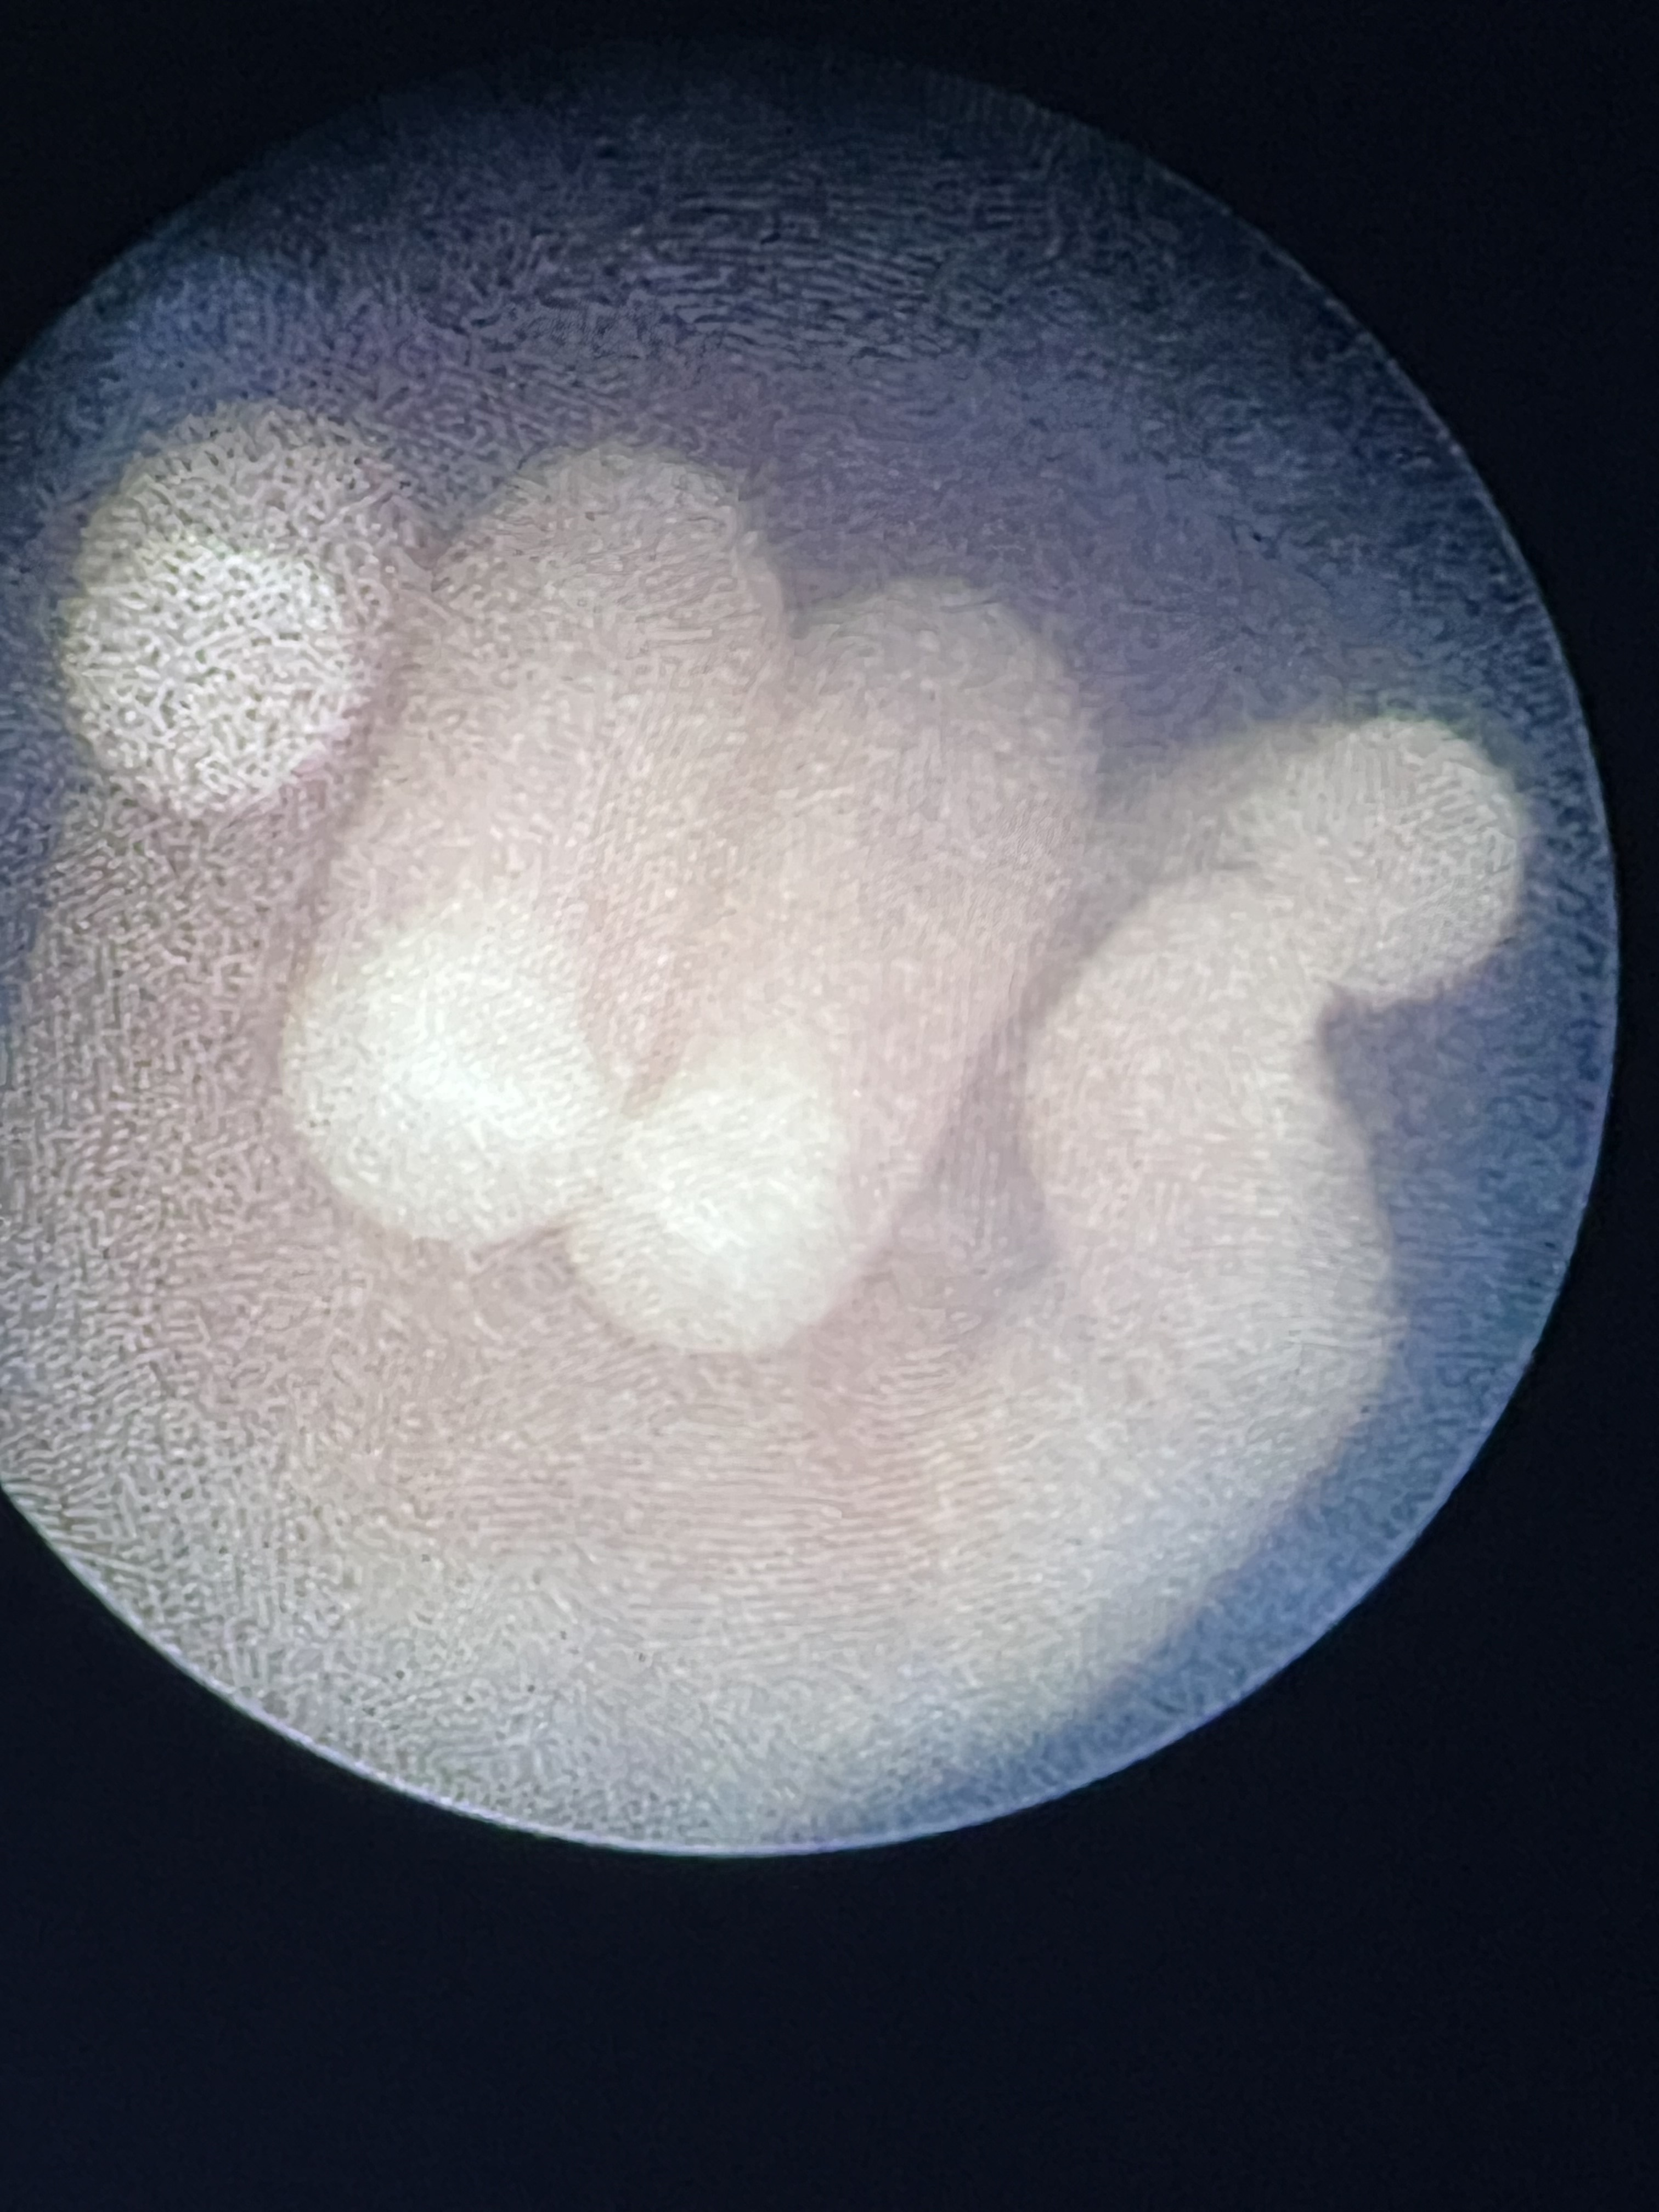

In this first case for the hospital, the mother presented with significant TTTS complications. The recipient fetus was experiencing heart failure and an accumulation of fluid in the abdominal and chest cavities. Banner’s fetal surgery team used a fetoscope inserted into the uterus through a small incision in the mother’s abdomen to close the twin fetus’ abnormal blood vessel connections and restored equal blood flow.

TTTS face

TTTS hand